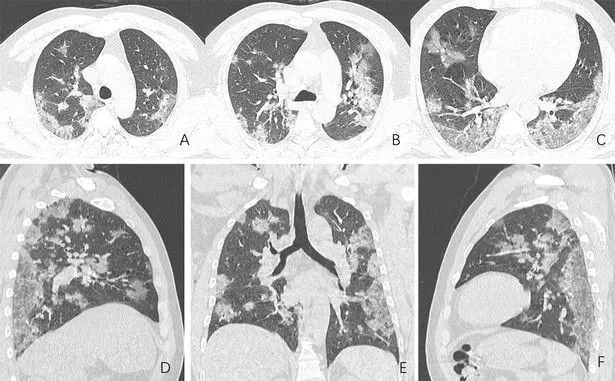

Οι σαρώσεις του, που δόθηκαν στη δημοσιότητα από την Ακτινολογική Εταιρεία της Βόρειας Αμερικής, δείχνουν λευκά στίγματα στις κάτω γωνίες των πνευμόνων του, πράγμα που υποδηλώνει τη μερική πλήρωση των αεραγωγών.

Και όταν συγκρίνουμε την εικόνα Α με την εικόνα F, δείχνει πώς το υγρό στους χώρους των πνευμόνων του ανθρώπου έγινε πιο έντονο με την πάροδο του χρόνου.

Οι γιατροί λένε ότι αυτές οι ανωμαλίες που εντοπίστηκαν είναι παρόμοιες με εκείνες που εντοπίζονται σε ασθενείς που πάσχουν από παρεμφερείς αιτίες σοβαρών οξέων αναπνευστικών συνδρόμων (SARS) και αναπνευστικού συνδρόμου στη Μέση Ανατολή (MERS).